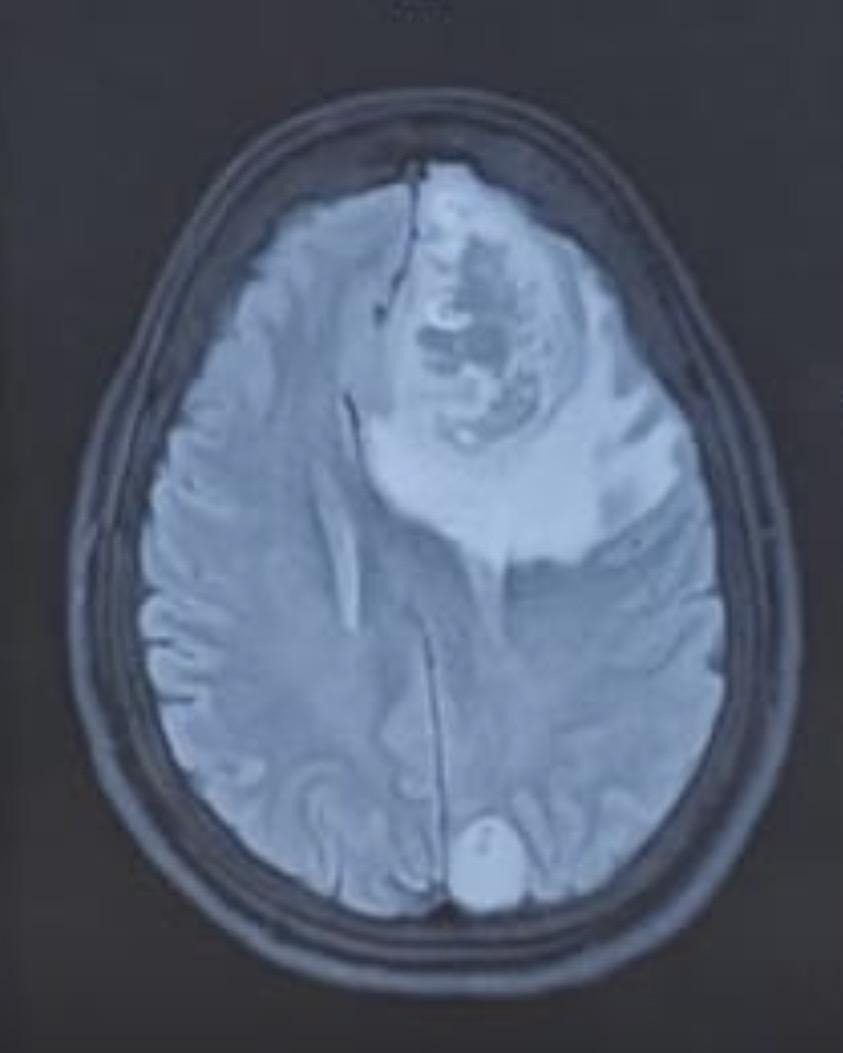

A brain tumor is the growth of abnormal cells in the brain. These may be of different types – benign, i.e., non-growing mass, and malignant, i.e., proliferative growing masses.

Neuro Oncology is the field of medicine that combines neurology and oncology, i.e. it deals with the treatment of cancers of the brain and spine.

Comprehensive diagnosis, personalised treatment plans, and multidisciplinary expertise to help you fight brain tumour with confidence and clarity